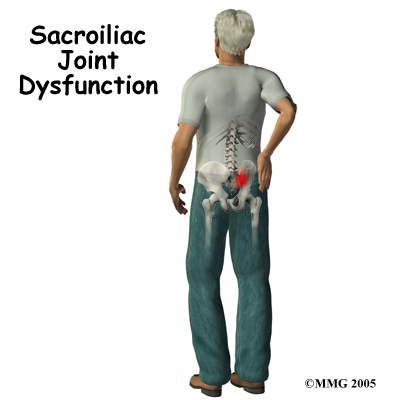

A painful Sacroiliac (SI) joint is one of the more common causes of mechanical low back pain. A ‘dysfunction’ of the SI joint is a term that is used to describe the pain associated with this joint because it is often still unclear why this joint becomes painful and leads to low back pain. Most people who suffer from this problem can reduce the pain with physical therapy treatment and manage the problem.

Most commonly the pain from an SI joint dysfunction is either directly over the SI joint itself or may radiate pain lower down into the buttocks. The pain may affect one side or both SI joints. Most times the pain from an irritable SI joint remains well above the knee, but in a few cases it can radiate down the leg all the way to the foot and may be confused with a herniated disc of the lumbar spine. The pain may also radiate into the groin area. People often feel muscle spasm or tightness in one or both of their buttocks muscles when the SI joint is affected.

Most commonly the pain from an SI joint dysfunction is either directly over the SI joint itself or may radiate pain lower down into the buttocks. The pain may affect one side or both SI joints. Most times the pain from an irritable SI joint remains well above the knee, but in a few cases it can radiate down the leg all the way to the foot and may be confused with a herniated disc of the lumbar spine. The pain may also radiate into the groin area. People often feel muscle spasm or tightness in one or both of their buttocks muscles when the SI joint is affected.

Problems with the SI joint may make sitting difficult. Pain in one SI joint may cause a person to sit with that buttock tilted up as it is often uncomfortable to sit flat in a chair. Walking can also be very painful depending on the degree of irritability of the joint and whether or not the joint is considered to have too much movement or is deemed stiff. Increased motion at the joint, such as during pregnancy, can be a particularly debilitating problem which makes activities such as going up or down stairs, standing on one leg, putting on your shoes and socks, or getting in and out of a car difficult. Turning over in bed is also particularly difficult when the SI joint moves more than normal.

Most commonly the pain from an SI joint dysfunction is either directly over the SI joint itself or may radiate pain lower down into the buttocks. The pain may affect one side or both SI joints. Most times the pain from an irritable SI joint remains well above the knee, but in a few cases it can radiate down the leg all the way to the foot and may be confused with a herniated disc of the lumbar spine. The pain may also radiate into the groin area. People often feel muscle spasm or tightness in one or both of their buttocks muscles when the SI joint is affected.

Most commonly the pain from an SI joint dysfunction is either directly over the SI joint itself or may radiate pain lower down into the buttocks. The pain may affect one side or both SI joints. Most times the pain from an irritable SI joint remains well above the knee, but in a few cases it can radiate down the leg all the way to the foot and may be confused with a herniated disc of the lumbar spine. The pain may also radiate into the groin area. People often feel muscle spasm or tightness in one or both of their buttocks muscles when the SI joint is affected.